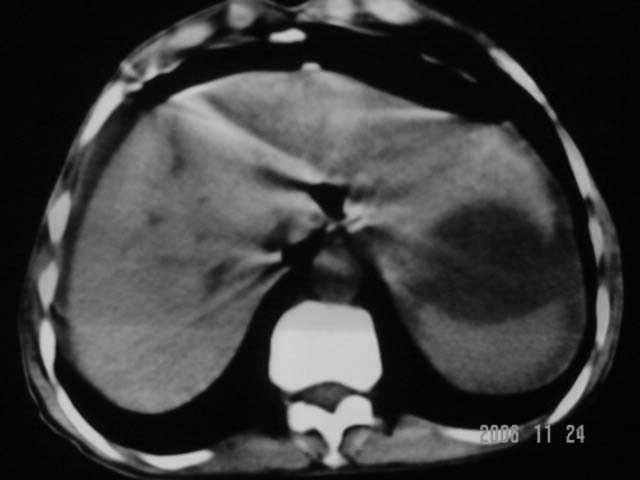

仰卧位见:肝前间隙及肝脾间隙内可见新月形气体密度影,边缘清楚,侧卧位见气体随体位改变而移动,ct值约-929hu。膈下、肝下间隙及部分肠间隙可见液性密度影。考虑:1、上腹部空腔脏器穿孔,以胃穿孔可能性大。2、少量腹水。

仰卧位见:肝前间隙及肝脾间隙内可见新月形气体密度影,边缘清楚,侧卧位见气体随体位改变而移动,ct值约-929hu。膈下、肝下间隙及部分肠间隙可见液性密度影。考虑:1、上腹部空腔脏器穿孔,结合临床,首先考虑胃穿孔可能性大。2、少量腹水

肝前间隙及肝脾间隙内可见新月形气体密度影,边缘清楚,侧卧位见气体随体位改变而移动,

考虑:1、消化道穿空